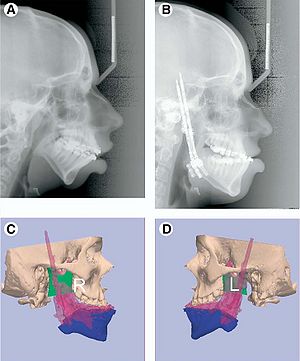

Boolean Combinations of Implicit Functions for Model Clipping in Computer-Assisted Surgical Planning

Publication: PLoS One. 2016 Jan 11;11(1):e0145987. PMID: 26751685 | PDF Authors: Zhan Q, Chen X. Institution: School of Mechanical Engineering, Shanghai Jiao Tong University, Shanghai, China. Background/Purpose: This paper proposes an interactive method of model clipping for computer-assisted surgical planning. The model is separated by a data filter that is defined by the implicit function of the clipping path. Being interactive to surgeons, the clipping path that is composed of the plane widgets can be manually repositioned along the desirable presurgical path, which means that surgeons can produce any accurate shape of the clipped model. The implicit function is acquired through a recursive algorithm based on the Boolean combinations (including Boolean union and Boolean intersection) of a series of plane widgets' implicit functions. The algorithm is evaluated as highly efficient because the best time performance of the algorithm is linear, which applies to most of the cases in the computer-assisted surgical planning. Based on the above stated algorithm, a user-friendly module named SmartModelClip is developed on the basis of Slicer platform and VTK. A number of arbitrary clipping paths have been tested. Experimental results of presurgical planning for three types of Le Fort fractures and for tumor removal demonstrate the high reliability and efficiency of our recursive algorithm and robustness of the module. Funding:

|

A snapshot of the module SmartModelClip in 3D Slicer. On the left is the operator command view that users can create and manipulate clipping path and thickness plane(i.e., they can create, hide and delete plane widgets). Users can also reverse the directions of the axes of the both clipping path and thickness plane widget. On the right is the scene that users can interact with the clipping path. They can specify the fiducial points that position the clipping path and modify the boundary of the clipping path by dragging the handles to obtain the desirable clipping path. |